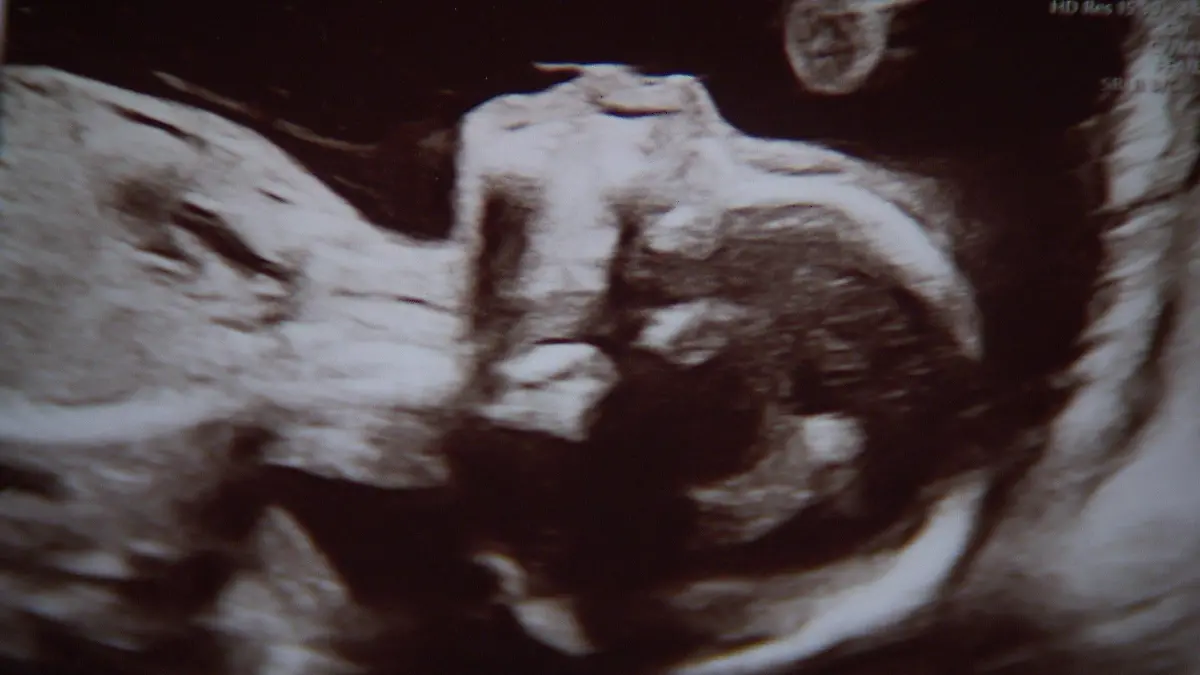

Nach vielen Untersuchungen wird klar: Das Baby ist gesund. Die 40-Jährige entscheidet sich gegen weitere Krebsbehandlungen und für ihren ungeborenen Sohn. „Den Herzschlag hab ich schon gehört, man sieht einen Fuß oder mal eine Hand. Und dann darüber nachzudenken, das Kind sterben zu lassen? Zu welchem Preis? Diese Vorstellung, ins Krankenhaus zu gehen und zu sagen: ‘So, jetzt musst du sterben, ich nehme irgendein Medikament.’ Ich glaube, dann wäre die restliche Lebenszeit nicht mehr schön gewesen“, erzählt sie uns. Und weiter: „Zum Einen beschäftigt man sich mit dem Tod und was es heißt, zu sterben. Und zum Anderen wächst Leben in einem. Auch wenn ich irgendwann nicht mehr bin, ist trotzdem noch etwas von mir da. Wir haben auch schon eine Tochter. Das ist etwas Schönes in der doofen Zeit.“